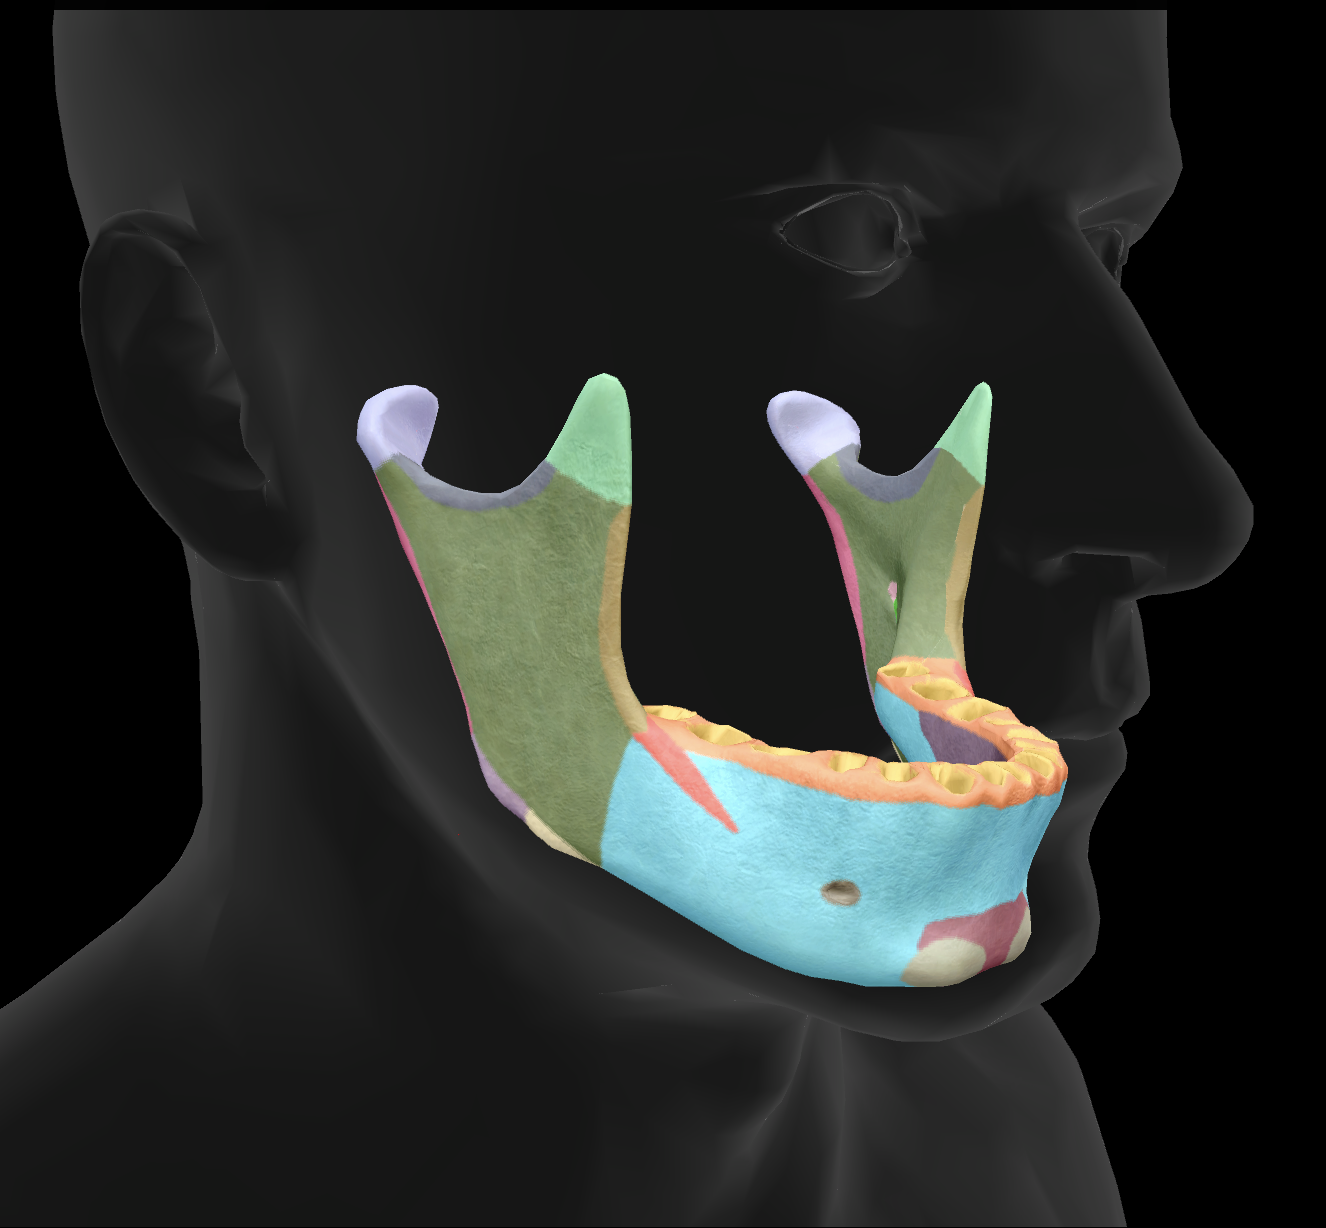

What bone is this?

mandible

What is the name of this feature?

mental foramen

What is the name of this feature?

mandibular condyles

What is the name of this feature?

ramus

What is the name of this feature?

alveolar process

What is the name of this feature?

mandibular notch

What is the name of this feature?

angle

What is the name of this feature?

body

What is the name of this feature?

coronoid process

What is the name of this feature?

mental protuberance